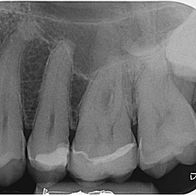

Orthograde Revisionsbehandlung

vorhandener Wurzelkanalfüllungen

vorher

nachher